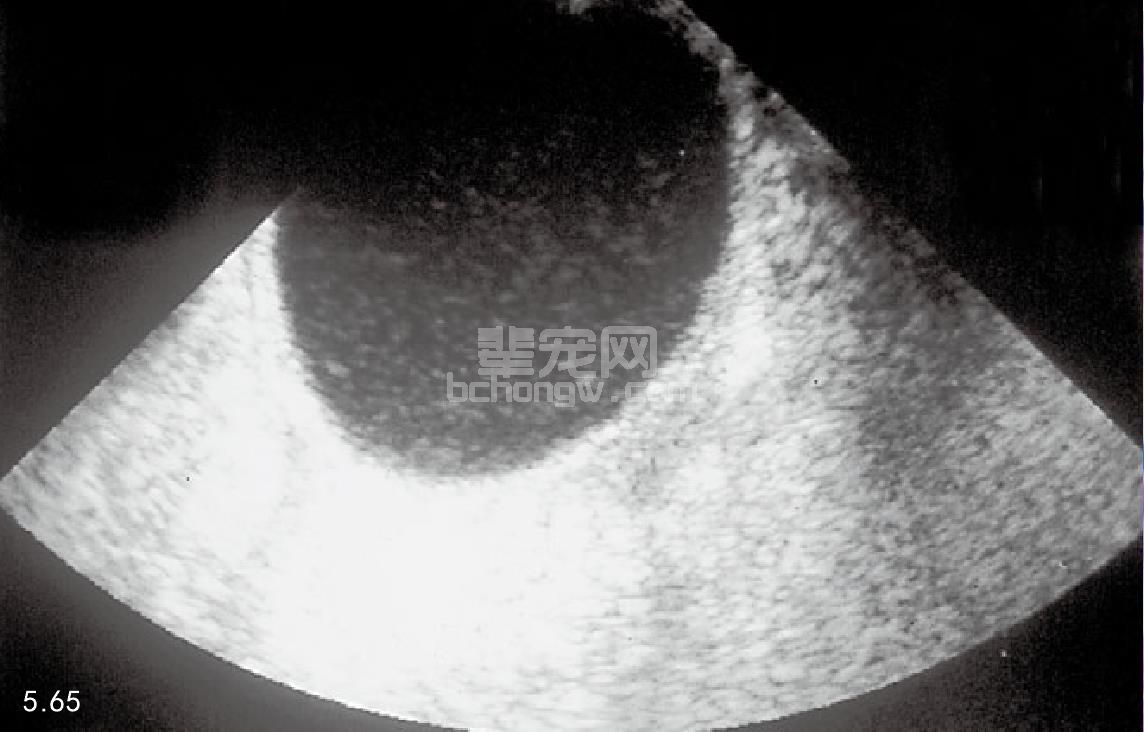

诊断 直肠检查骨盆腔偏移直肠可以检查到囊肿。前列腺周囊肿非常大时其腹部也会增大。使用放射学检 查可以显示腹腔后部的影像细节不清,囊肿壁钙化。在X线平片上很难区分囊肿和膀胱的位置,通过膀胱造影 或者超声诊断可以解决这个问题。如果囊肿没有发生感染,超声检查会显示有低回声囊肿液体的薄壁囊肿(图 5.65)。抽吸的液体通常为黄色,但是可能是血清样物质或相关的非细胞成分,有时没有结果。如果怀疑有继发 性感染,不宜使用细针进行抽吸,因为囊肿的壁很薄,即使是很细的针穿刺也会使里面的液体漏出。

图5.65 德国牧羊犬在小骨盆腔中的前列腺周囊肿的超声诊断图像。该图像是使用直肠探头获得的。